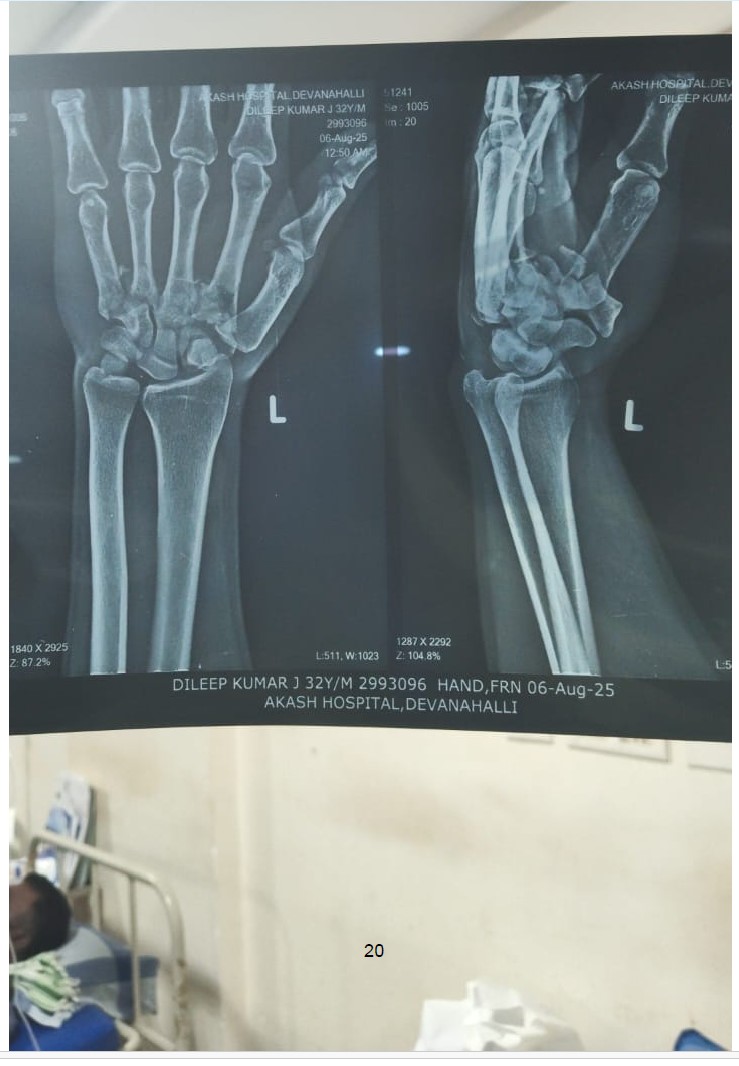

Dileep J, a 31-year-old young man, met with a devastating road traffic accident (RTA) that left him with severe trauma to his left brachial plexus. This injury has led to complete motor loss (0/5) and sensory loss across multiple nerve levels (C5 to T1), affecting his ability to use his arm and shoulder. MRI and CT reports reveal extensive damage, including thickened nerve trunks, fluid accumulation, and edema in both superficial and deep tissues of the neck and chest.

Despite the severity, his spinal cord remains intact, giving hope for recovery if prompt medical intervention is provided. Doctors have recommended further treatment and a follow-up scan after three months to assess nerve healing and potential for surgical repair or advanced therapy.